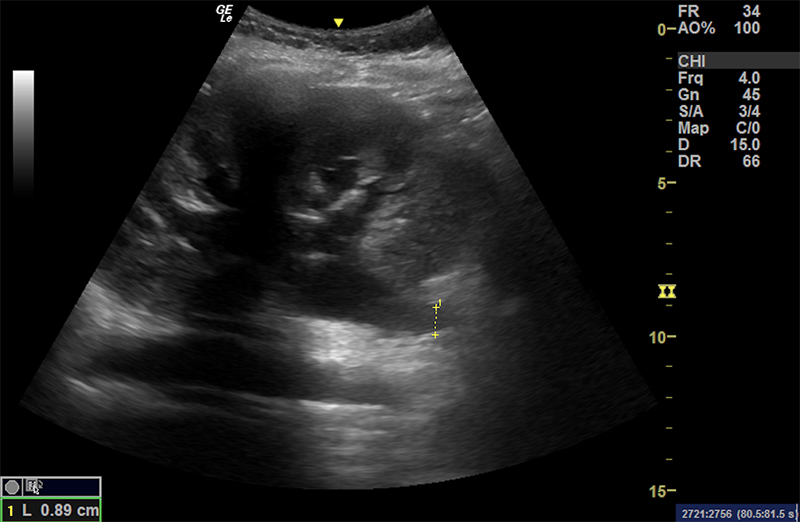

Figure 49. Mild hydronephrosis seen on long axis view of the kidney. Note the mild dilation of the renal pelvis and calyces and the lack of color Doppler flow over the anechoic (black) dilation of the renal pelvis.